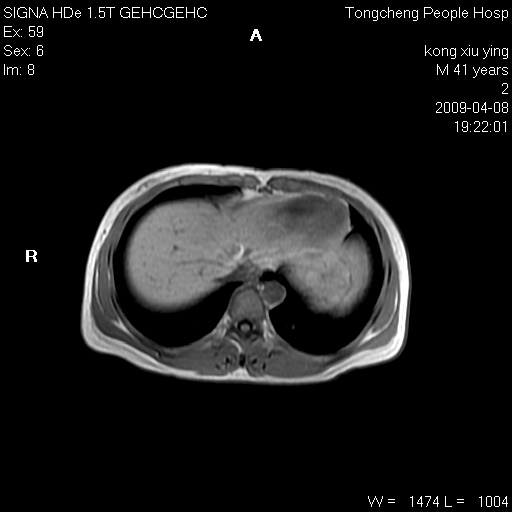

标题: CL1008:【经典】胆囊石榴籽样结石。

女,41岁。健康体检——彩超提示:胆囊显示不清。平素健康,无不适感。

腹部mr扫描及mrcp,图像如下: